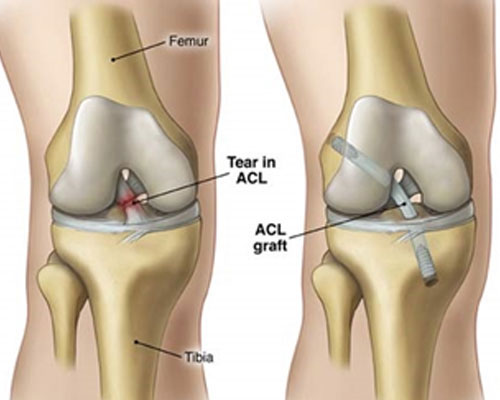

Arthroscopy

Arthroscopy is a procedure for diagnosing and treating joint problems. A surgeon inserts a narrow tube attached to a fiber-optic video camera through a small incision — about the size of a buttonhole. The view inside your joint is transmitted to a high-definition video monitor.